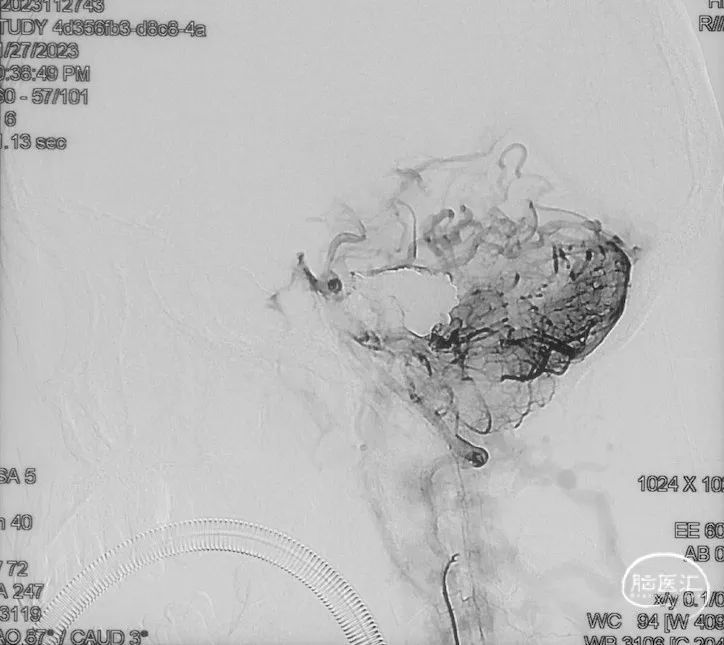

治疗过程

选取工作角度,正侧位造影

Echelon-10微导管在ASAHI 0.010微导丝导引下经右侧脑膜中动脉分支超选至瘘口,可见瘘口口径大,微导管直接越过瘘口,进入引流静脉起始部。

Marathon微导管在ASAHI 0.010微导丝导引下经右侧脑膜中动脉分支超选至瘘口近端。

经Marathon微导管手推造影明确微导管位于瘘口动脉端,Echelon-10微导管位于瘘口引流静脉起始端处扩张的静脉球内。

由于瘘口流量大,为了防止栓塞材料过度弥散,并逃逸至深静脉,首先通过Echelon-10微导管向静脉球内填入Feng 12/40、Feng 10/30两枚弹簧圈,限制后续液态栓塞材料仅在静脉起始部弥散。

随后回撤Echelon-10微导管,并通过Echelon-10微导管和Marathon微导管交替注入Onyx-34、Onyx-18,此时可见Onyx首先被血流冲至静脉球内,但被弹簧圈篮筐限制,并在瘘口范围内弥散。

通过“注射-停顿-再注射”,Onyx进一步在瘘口及供血动脉段和引流静脉起始部弥散满意

造影显示瘘口不显影,无静脉早显。